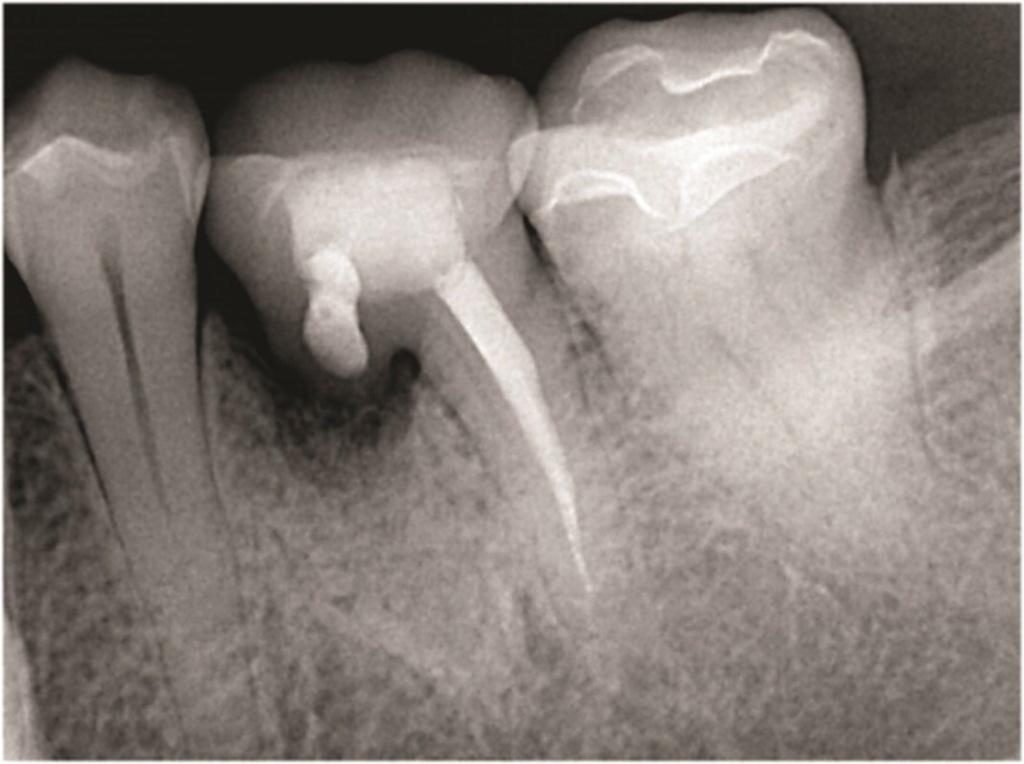

Фото 3: Зуб 3.6 с латеральной и апикальной потерей кости в области переломанного мезиального корня.